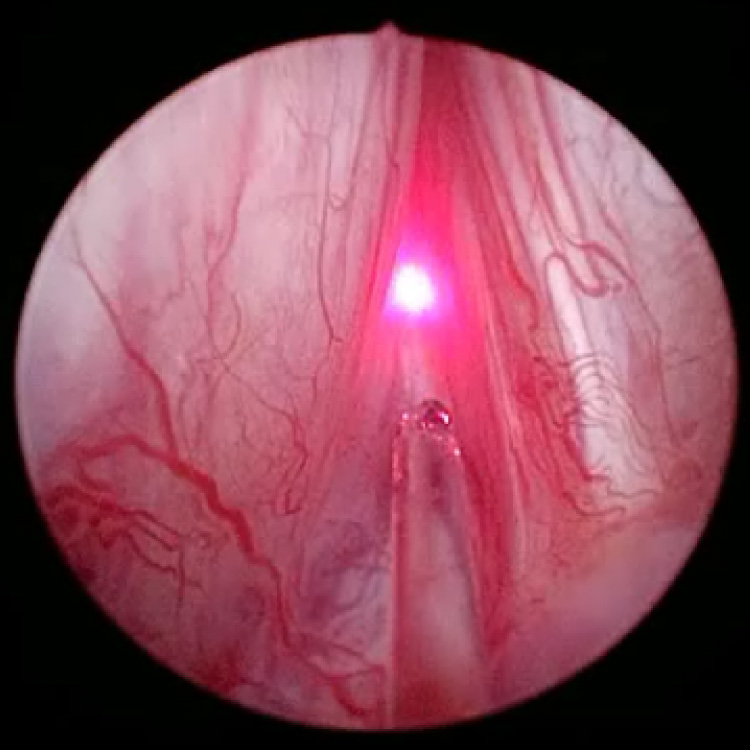

HoLEP

尿道を閉塞する前立腺腺腫

ホルミウムレーザーによる腺腫の核出(内腺のくり抜き)

腺腫の核出後